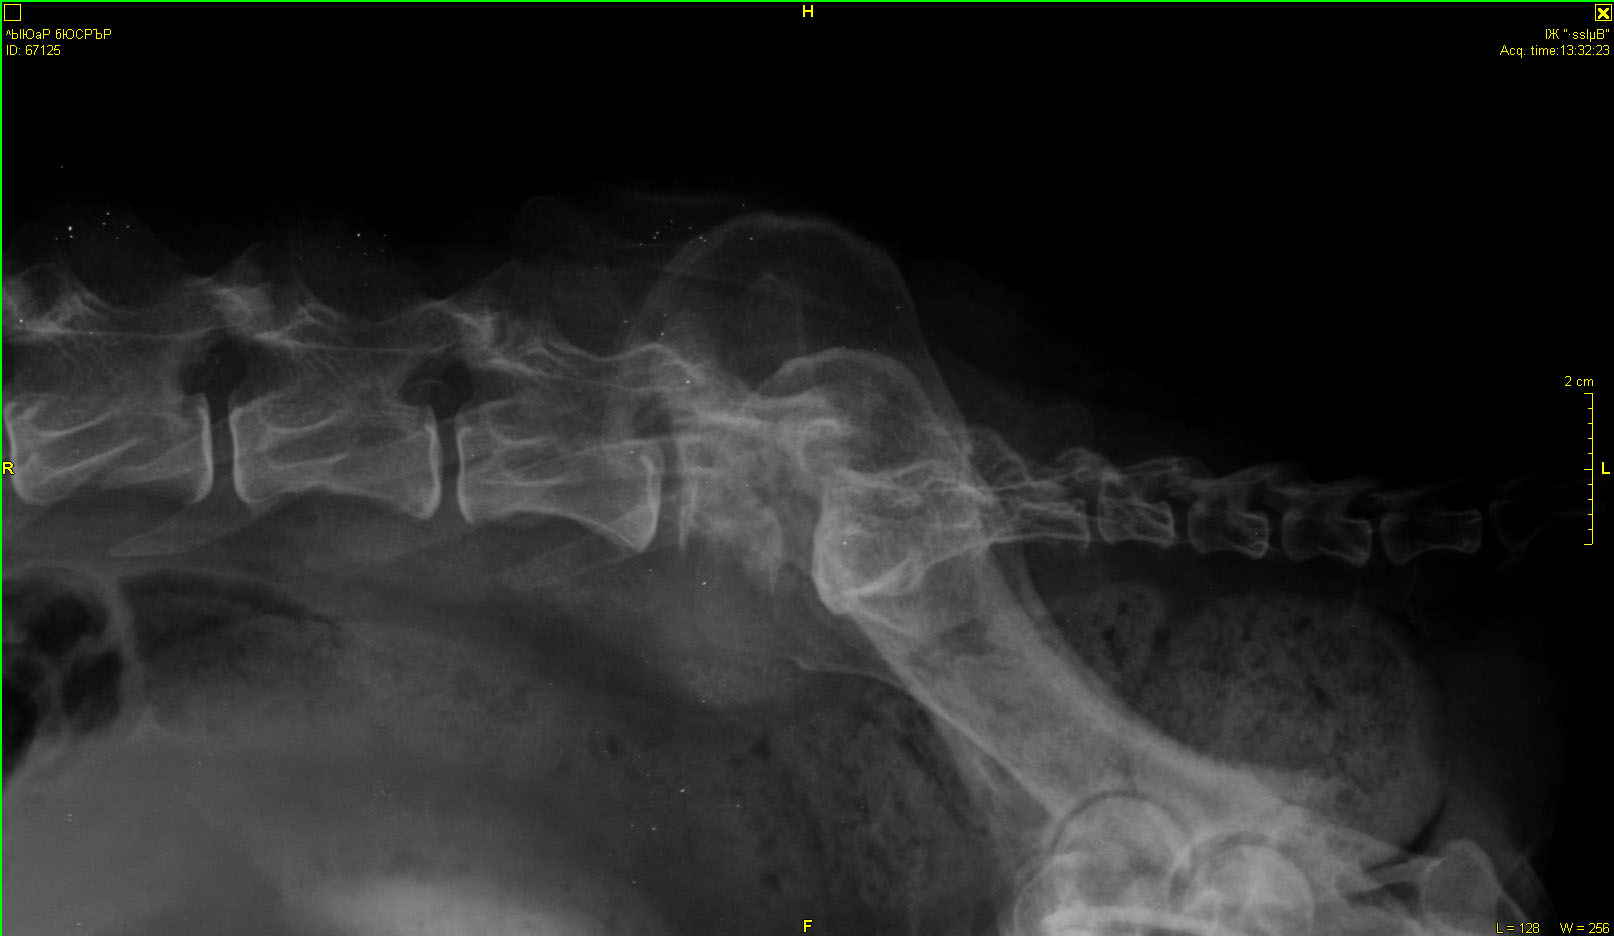

Рентген в Зоовете. Может, кто разбирается, что скажет?

"Вкратце. Новообразования в мочевом пузыре и в позвоночнике, раздробился позвонок, про который думали, что перелом. Был уж там перелом раньше или нет, сейчас уже не важно. Проблемы с мочевым - сам не мочится, только когда переполняется, но переполняться нельзя. Спасаемся катетером. Ну и плюс, конечно, повреждения спинного мозга, сильная обезвоженость, интоксикация, я всего не запомнила, Галина Юрьевна больше во всём разбирается, я выложу сейчас результаты анализов. Капельницы по 4 часа 2 раза в день, сейчас капается. Врач ставит онкологию, скорее всего злокачественную, это не достоверно, но скорее всего. Операцию смысла делать нет, потому что в её состоянии она не выдержит. Предложил или усыпить сразу, или капать и смотреть дальше по состоянию. Он не уверен, что она проживёт и более 5 дней. Хотя вот вчера и сегодня утром чуть курочки поела, сейчас ещё попробую дать. Но слабая конечно. Постоянно пьёт. Сейчас всё сосканирую и выложу.

Хотим показать результаты обследований Гаранину. Может быть, если состояние улучшиться, рискнём на операцию. Или во Владимире Ильину. "